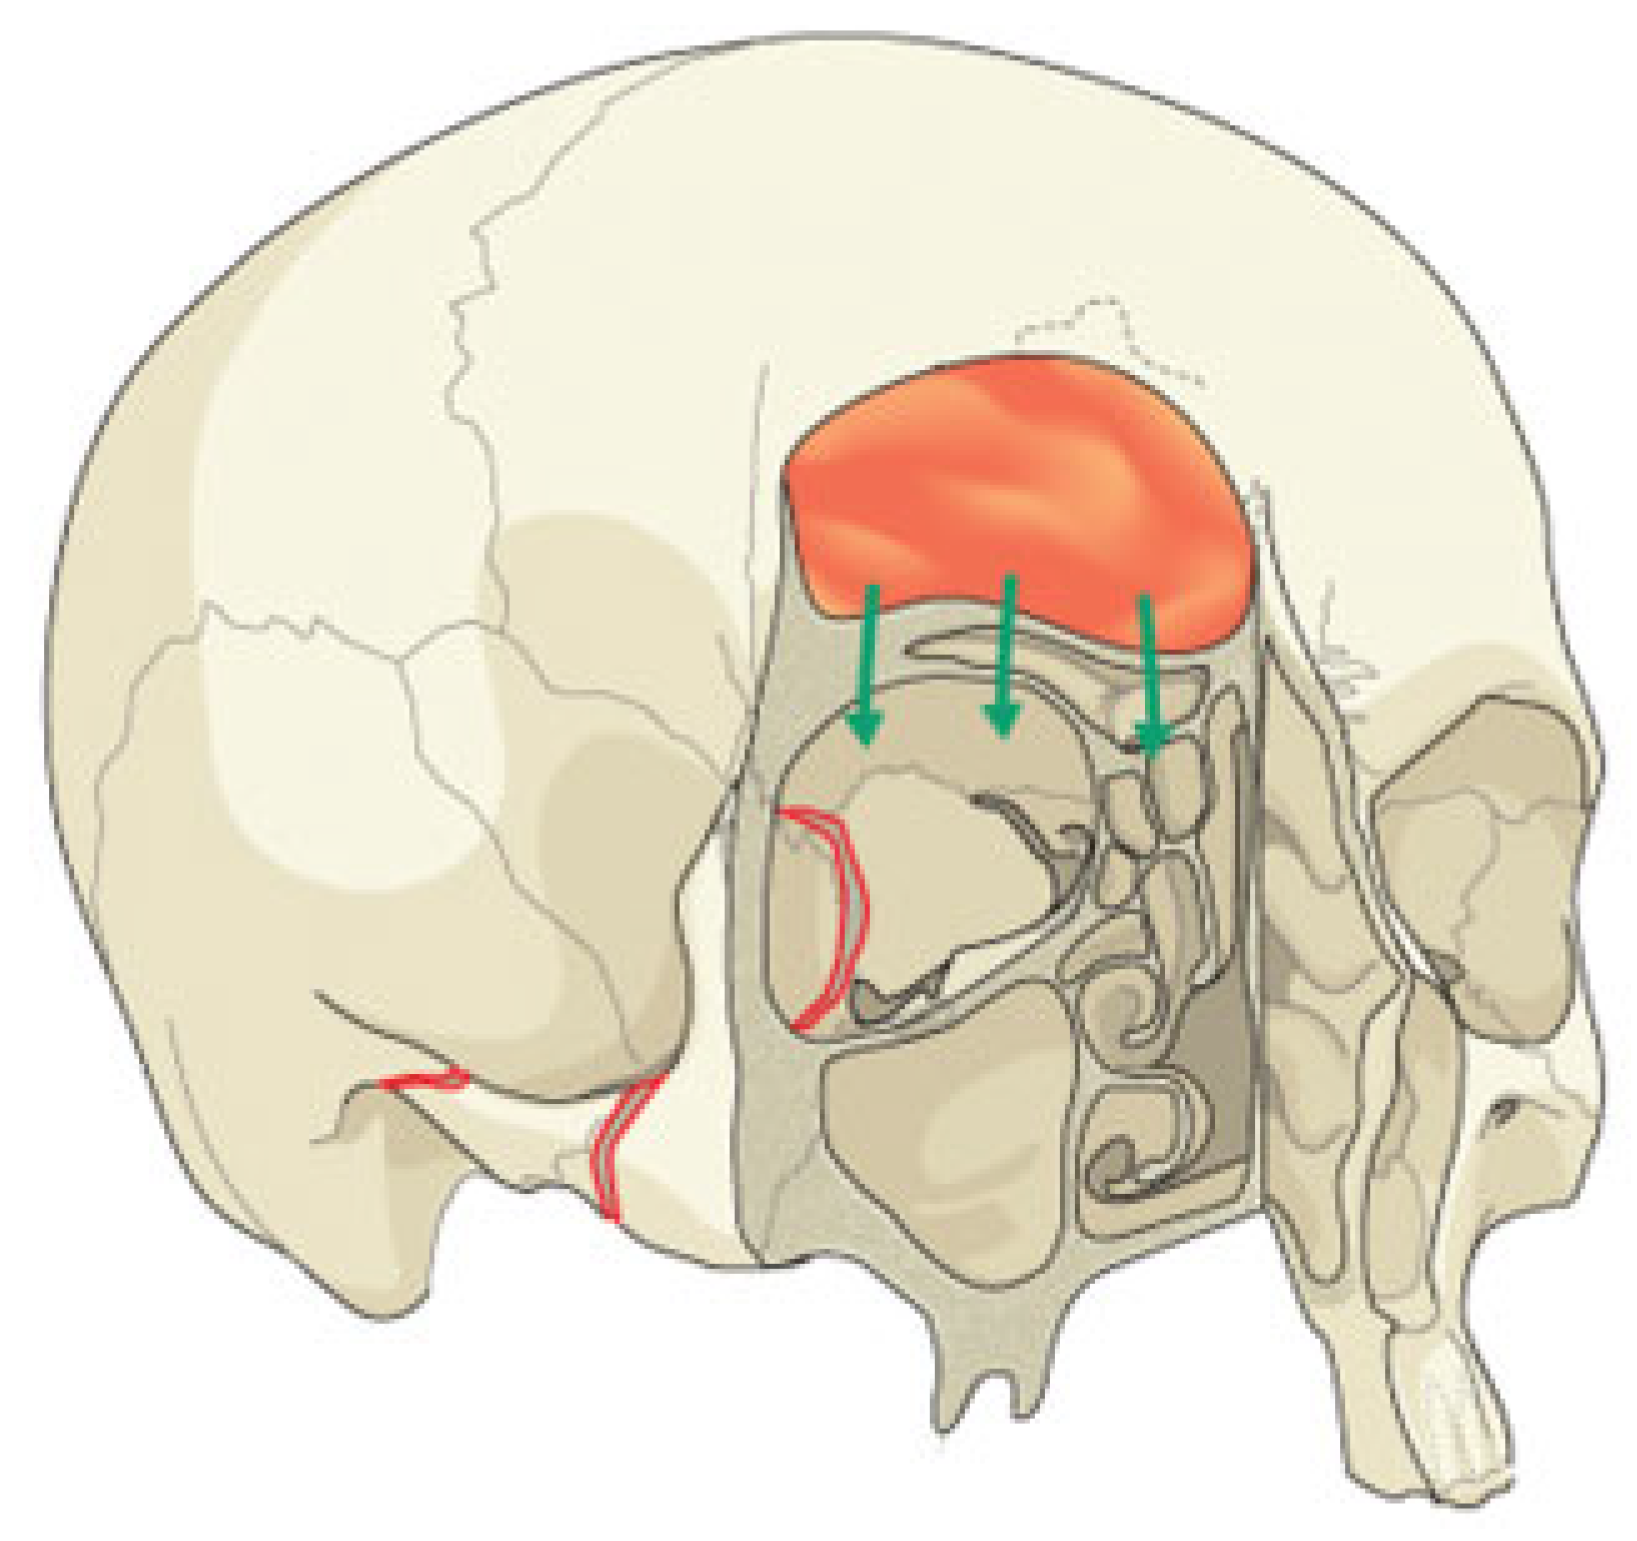

Figure 6. Orbital floor fracture. On this coronal section of a maxillofacial computed tomography scan, orbital contents can be visualized within the maxillary sinus.

Advances in the realm of CT have greatly enhanced diagnosis and preoperative planning. Nonetheless, in the pediatric patient, the immature craniofacial skeleton may obscure fracture lines, complicating the radiographic evaluation [22]. Sections are generally taken 1.25 mm apart. Coronal reformatting is frequently performed to further delineate fracture lines in alternate planes. Coronal views are crucial in evaluating the orbital floor. Three-dimensional CT permits further analysis of fracture patterns [23]. With this modality, volume and proportionality may be directly assessed. Care must be taken in the interpretation of three-dimensional images of the craniofacial skeleton—particularly those involving the orbit. The thin bones of the orbital floor and medial wall may be erroneously absent owing to the derivative nature of the formatting process. In reviewing the two-dimensional images of the CT scan, particular clues to the radiographic diagnosis of orbital fractures include the presence of step-off deformities along the orbital rim, orbital emphysema, and sinus opacification. In cases of orbital floor fracture, orbital contents may be seen herniating into the maxillary sinus (Figure 6). Conversely, the orbital floor may appear uninjured in spite of these findings, as the bone may recoil back into native position.